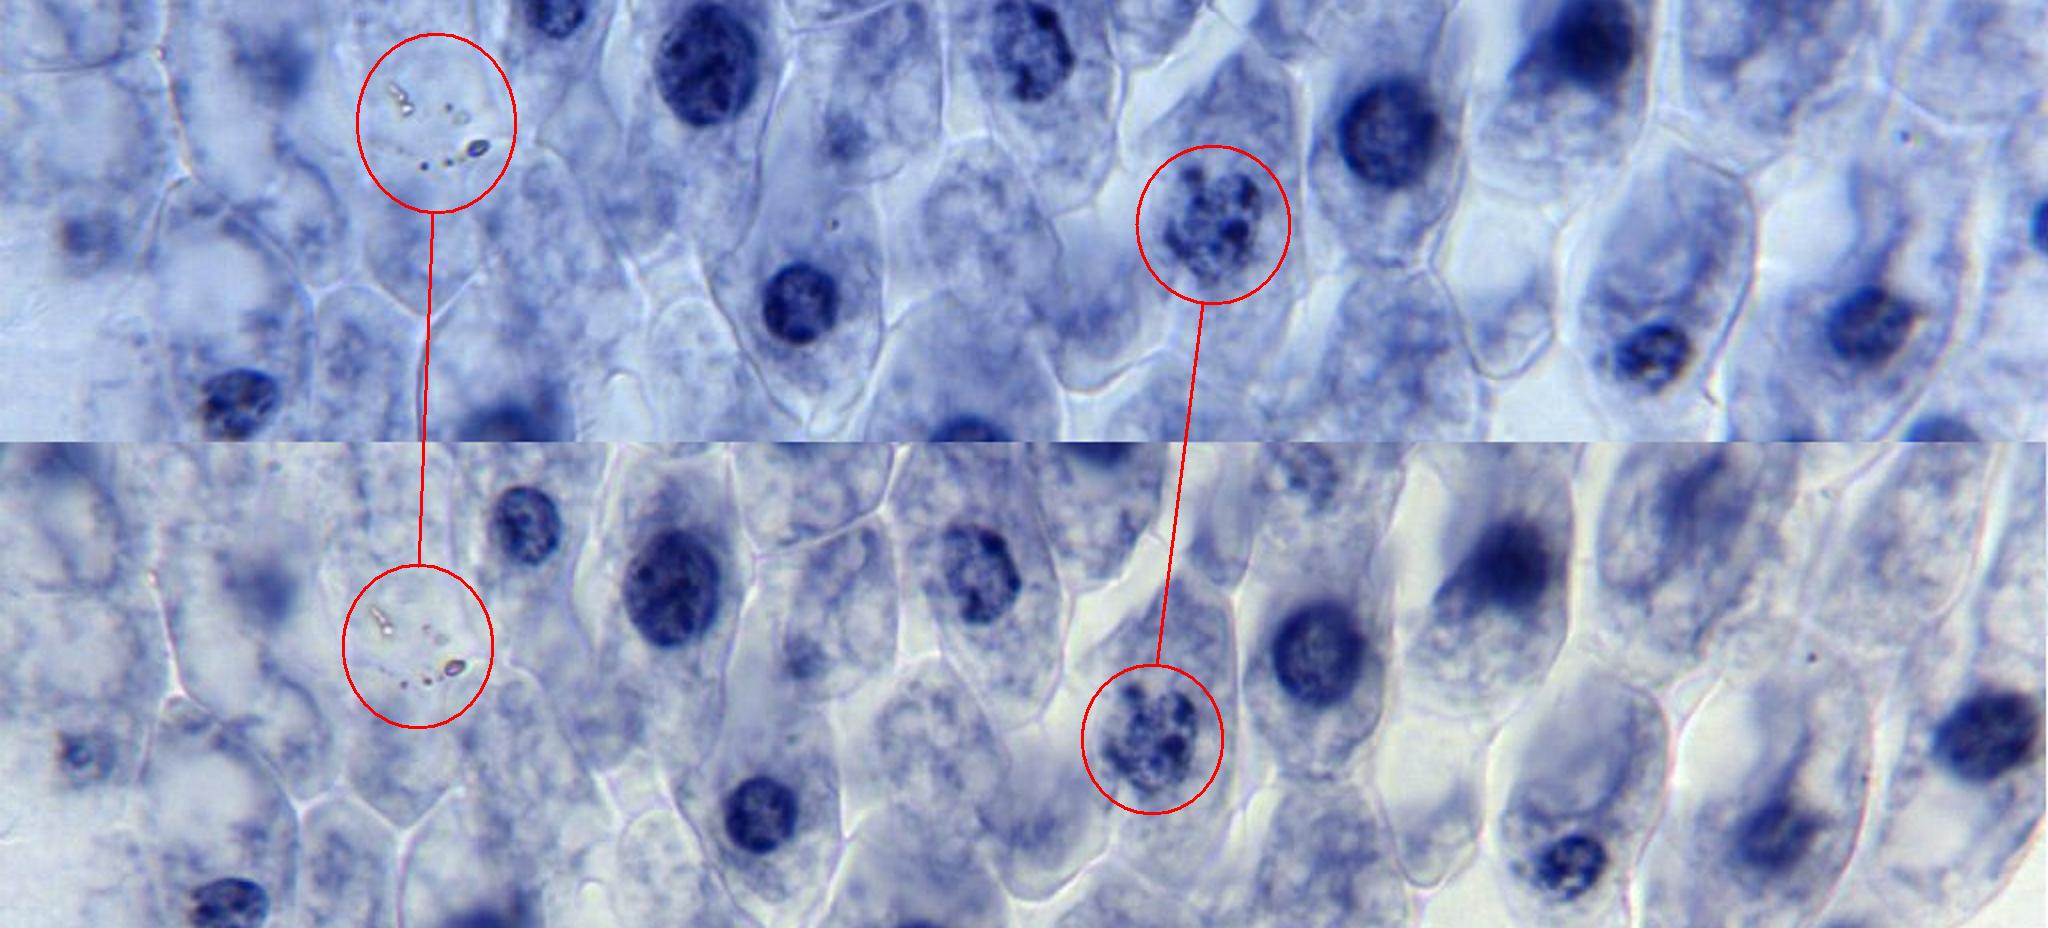

Sai che quasi quasi preferisco il secondo?

Immagine:

180,86 KB |